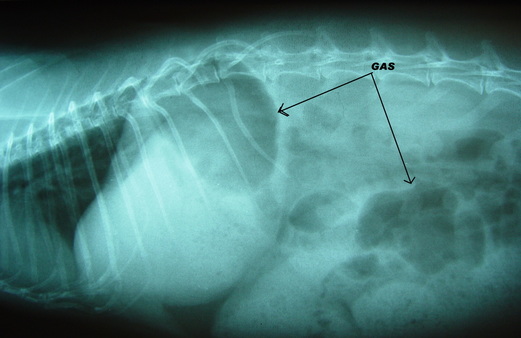

Every rabbit owner should be aware of GI stasis before it’s too late.